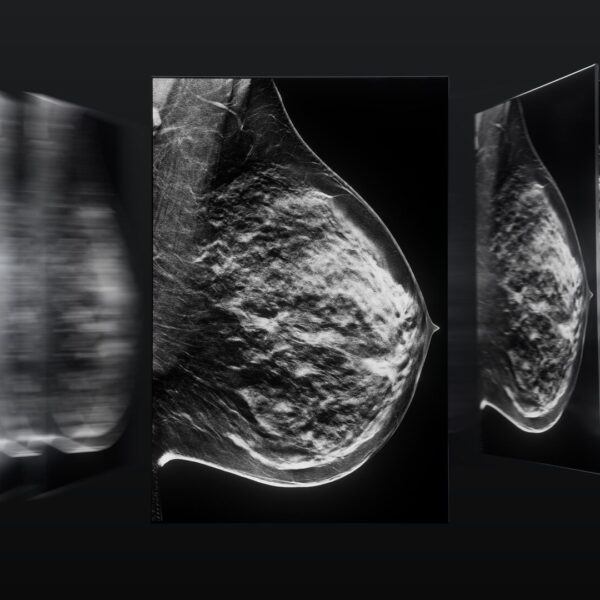

Borstbeeldvorming naar een hoger niveau

Het perspectief van prof. Gabor Forrai op de Barco Coronis OneLook

Professor Gabor Forrai, een ervaren radioloog uit Boedapest, Hongarije, draagt al meer dan drie decennia bij aan de vooruitgang in borstbeeldvorming. Met 35 jaar ervaring in mammografie, 28 jaar in borst-MRI en een leiderschapsrol als voormalig voorzitter van de European Society of Breast Imaging (EUSOBI), wordt professor Forrai gezien als een gerespecteerde autoriteit in het vakgebied. Zijn werk omvat universitaire ziekenhuizen, staatsinstellingen en privépraktijken, waar hij multidisciplinaire teams leidt en bijdraagt aan internationale onderwijsprogramma’s.

Eerste indrukken van de Coronis OneLook

Toen professor Forrai het Barco Coronis OneLook-display ontving voor testgebruik, zag hij meteen het potentieel om de diagnostische workflow te transformeren.

“De belangrijkste kenmerken van deze nieuwe Barco Coronis OneLook-monitor zijn het formaat, de resolutie , het contrast en de helderheid,” vertelt hij. De 32-megapixelmonitor biedt een grote sprong vooruit ten opzichte van eerdere modellen en stelt radiologen in staat om mammografiebeelden op volledige grootte te bekijken, zonder dat vergroting of het opsplitsen van beelden nodig is.

Een van de opvallende voordelen van de Coronis OneLook is het vermogen om te helpen bij het stroomlijnen van het diagnostische proces. Dankzij het ruime scherm en de hoge resolutie kunnen radiologen volledige beeldensets in één keer bekijken, waardoor de noodzaak om te scrollen of in te zoomen wordt verminderd.

Professor Forrai gelooft dat geavanceerde schermtechnologie zoals de Coronis OneLook een krachtig educatief hulpmiddel is. Voor radiologen in opleiding maakt het hoge contrast en de hoge resolutie het eenvoudiger subtiele afwijkingen, zoals microcalcificaties, te identificeren. “Voor radiologen aan het begin van hun carrière, zonder jarenlange ervaring, is dit verbluffend hoge contrast een groot voordeel,” zegt hij. “Ze zullen details gemakkelijker zien dan bij een scherm met laag contrast.”